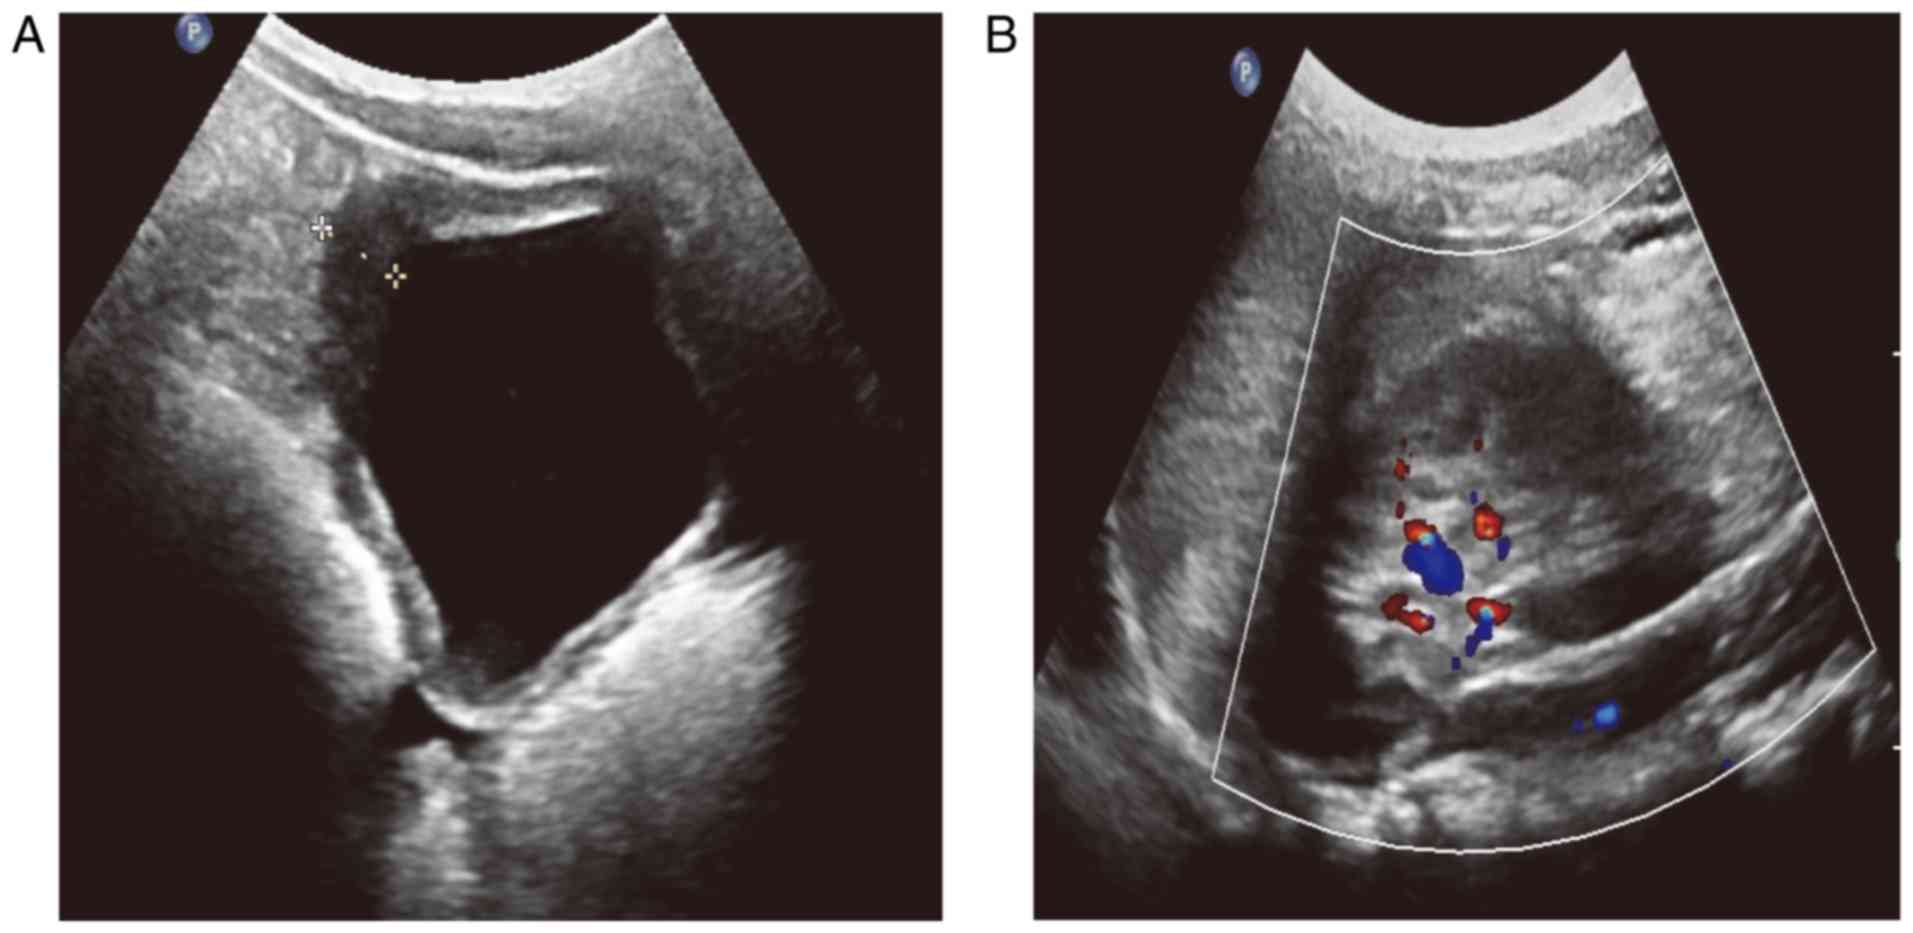

Cystitis Radiology Case Radiopaedia Org